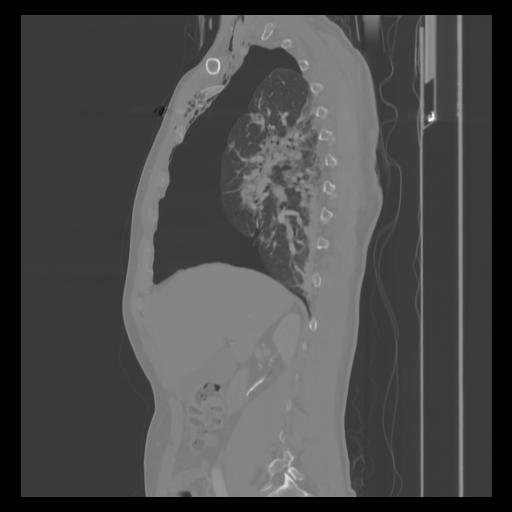

30 CUERPO,CE,Sagittal,3.000,CUERPO,Sagittal,